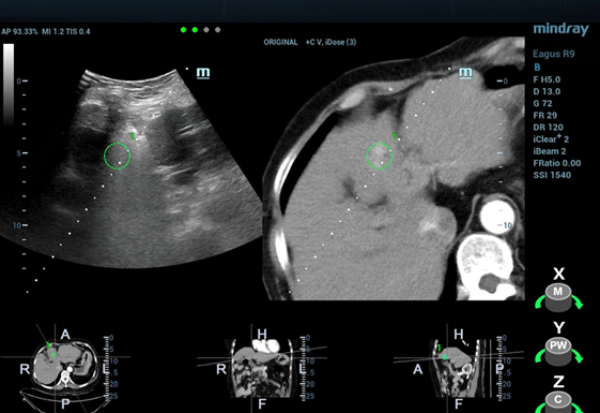

The patient was scheduled for ultrasound-guided microwave ablation (MWA), however, as the lesion could not be seen on conventional ultrasound, fusion imaging combining ultrasound imaging and contrast-enhanced CT (Clip 1, Figs. 4-7) was used to ensure accurate positioning of the microwave antenna.

The tumor was isoechoic and could not be clearly displayed using 2D grayscale ultrasound, therefore using conventional ultrasound guidance alone could result in inaccurate positioning and incomplete ablation. However, Fusion Imaging combining real-time ultrasound with the contrast-enhanced CT dataset allowed for accurate antenna positioning and successful treatment of the lesion by percutaneous MWA. CEUS was used pre-procedure to confirm tumor location and post-procedure to evaluate the ablation zone and ensure the efficacy of the treatment.